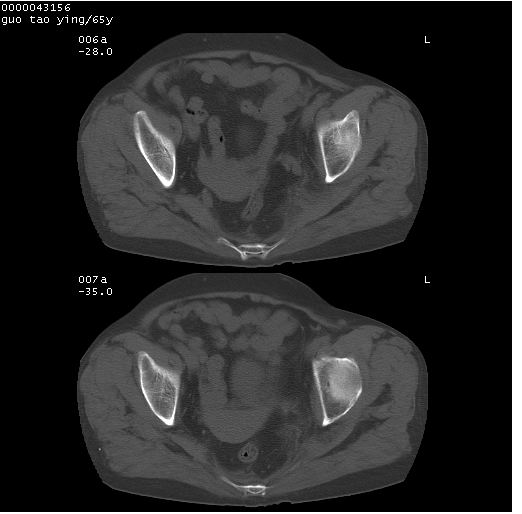

以下是引用黑白光影在2008-1-30 13:22:00的发言:[br]支持左耻骨骨折。[br]未见骶骨骨质明确破坏改变。[br]经楼主提示(勿局限于外伤)。考虑为右侧腹股沟直疝。[br][br][br][br]